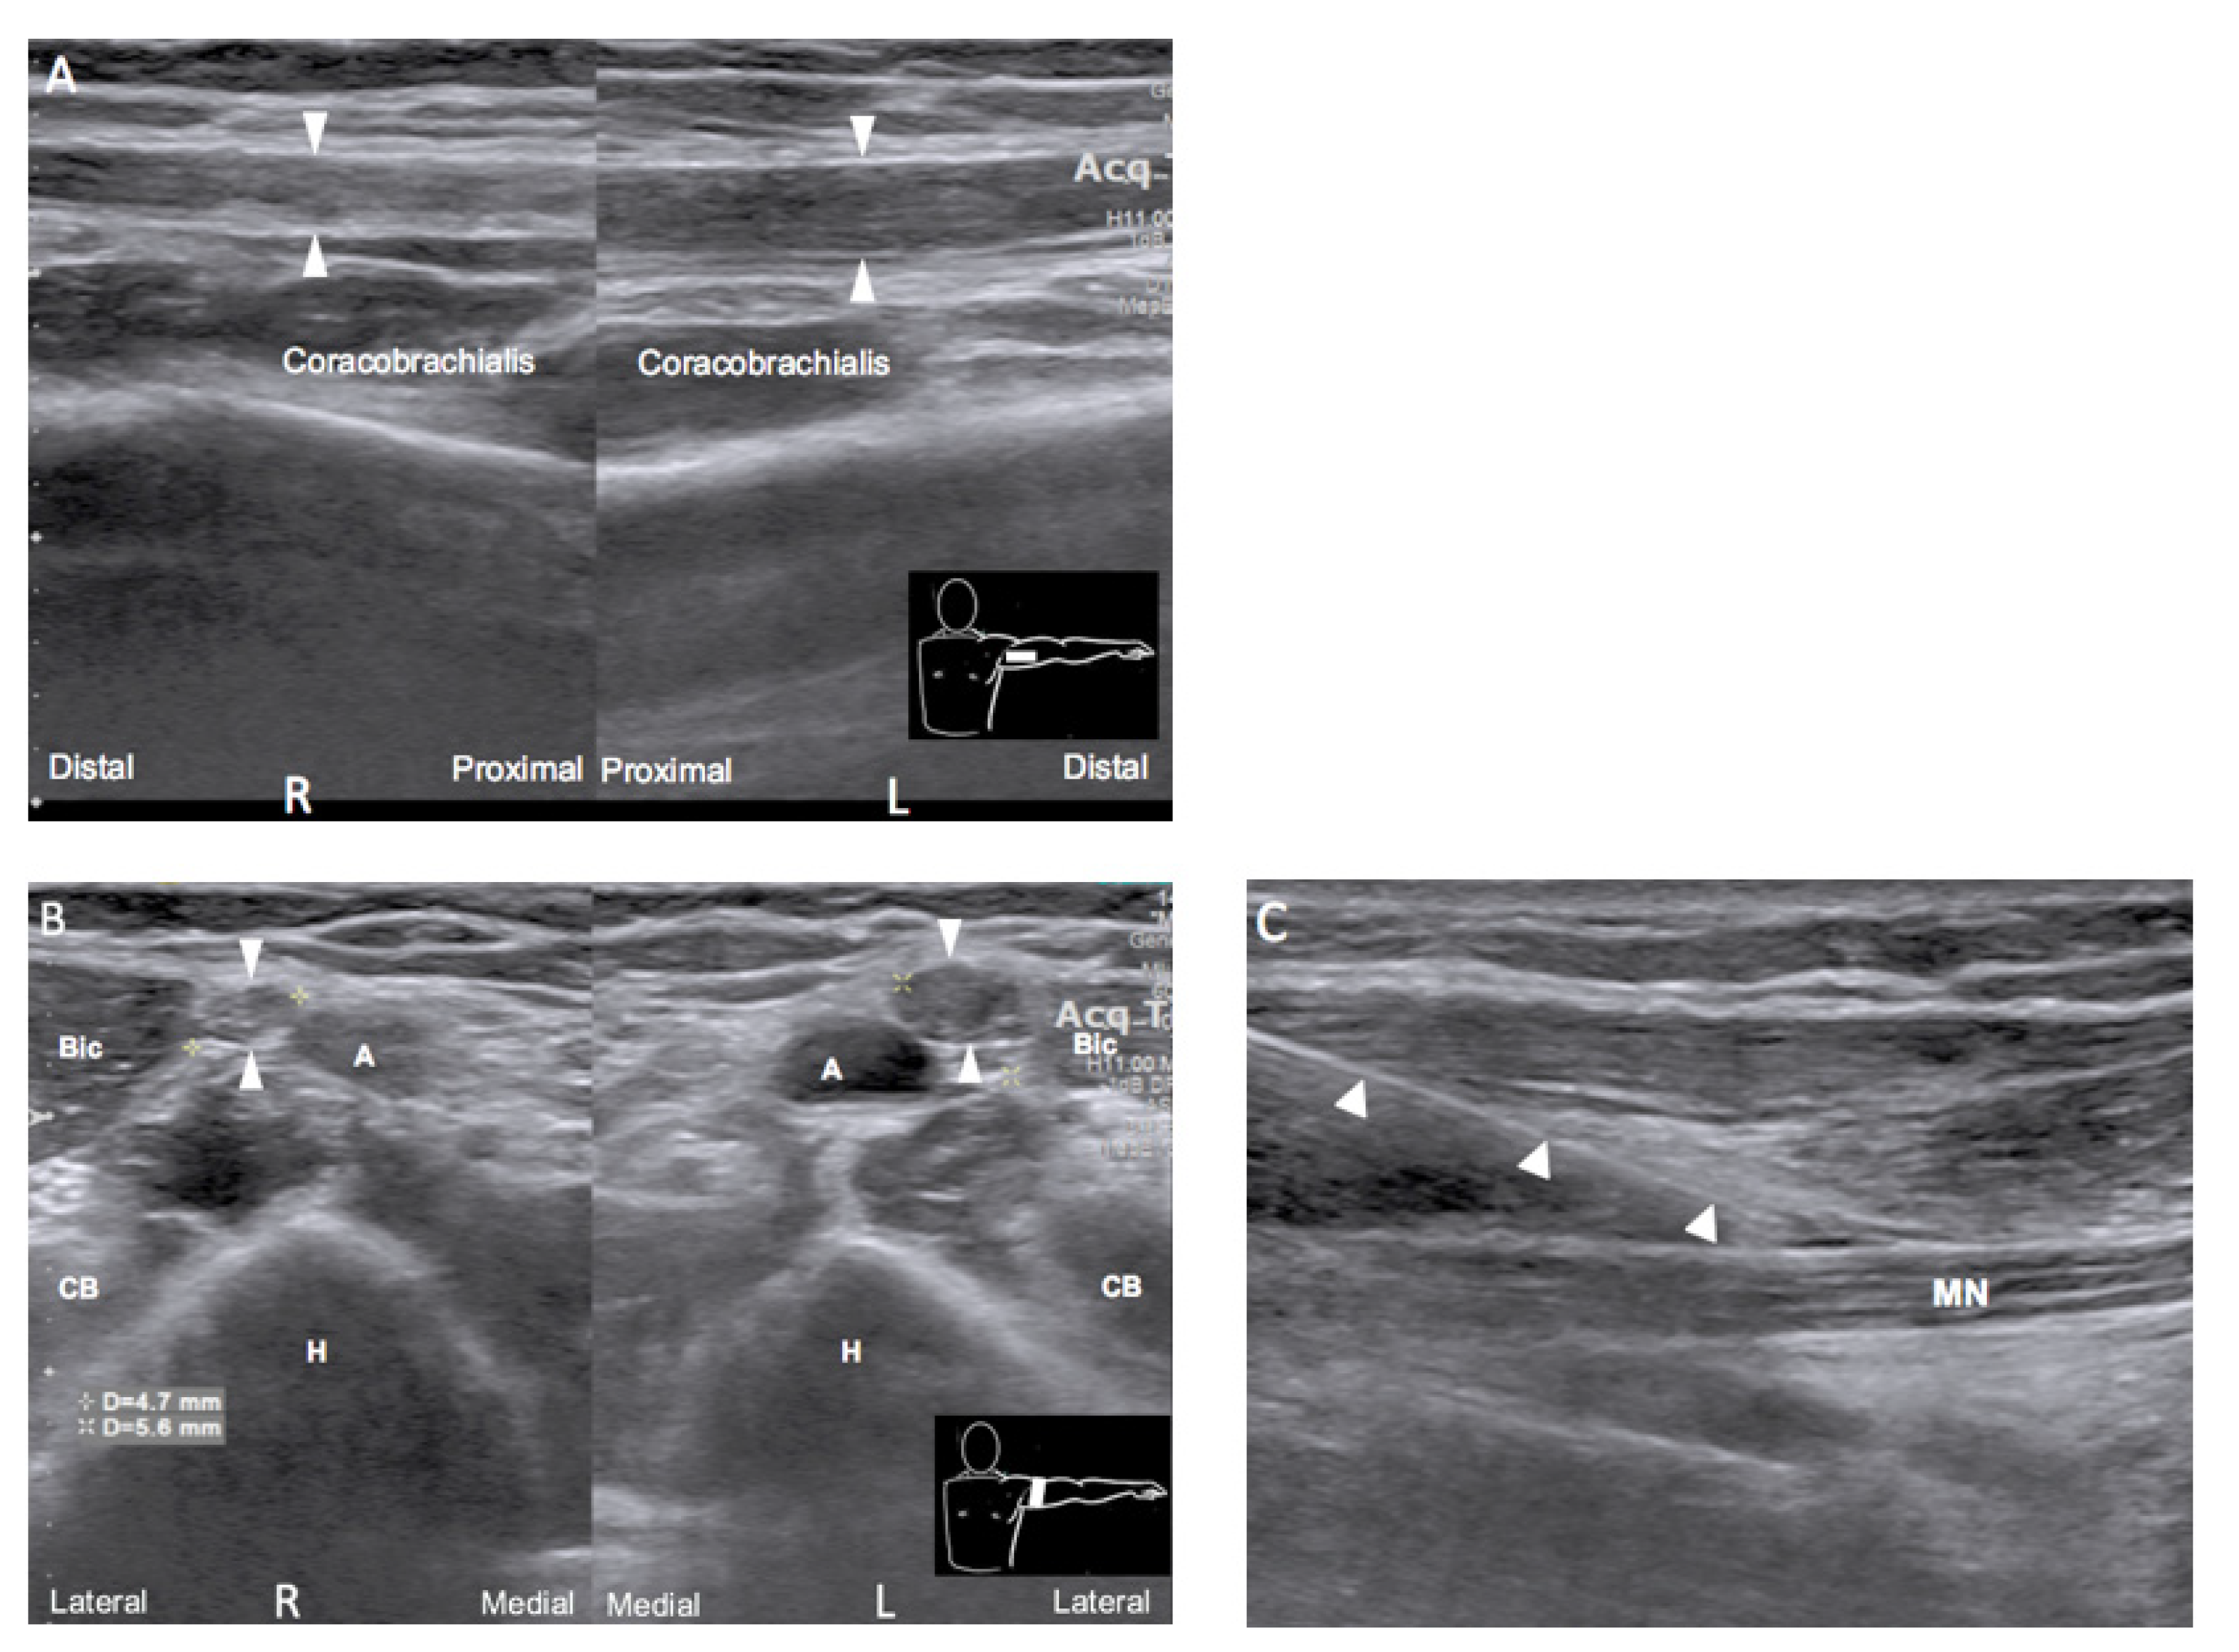

Ultrasound examination was performed simultaneously with electrodiagnostic examination to localize the lesion. A long segment of hypoechoic swelling of the left median nerve was noted from the axillary level until branching to AIN, by side-to-side comparison (Figure 1A,B). Ultrasound-guided hydrodissection of the left median nerve with corticosteroid administration over whole arm from axillary level to elbow (Figure 1C) was performed at the first month after injury after electrodiagnostic examination. The injection was performed twice with a two-week interval. A serial rehabilitation program, two times per week, including neuromuscular electrical stimulation and left forearm flexor strengthening exercises, was established.

Electrophysiological testing and ultrasonography are helpful tools for localizing the lesion in neuropathy. Our case showed decreasing amplitude and conduction velocity when stimulating the median nerve at the elbow and wrist with normal nerve conduction studies over the radial and ulnar nerves, which implies that the influence was on the median nerve rather than on the brachial plexus. The needle EMG suggested that the lesion was an isolated median neuropathy before branching to the FCR and well demonstrated the time course of neuropathy from the acute phase to the reinnervation phase. Nerve ultrasonography further confirmed the lesion at the axilla and showed the classical pattern of neuropathy, which is a hypoechoic and enlarged nerve at the axilla compared with that at the other side. Though MRI is widely used in evaluating brachial plexus injury, ultrasonography has advantages in focal resolution of individual peripheral nerve, accessibility, and without contraindication [10,11]. Meanwhile, ultrasonography can simultaneously being a guided tool for injection intervention.

Figure 1. Comparison of the bilateral median nerve at the axillary level in longitudinal view (A) and transverse view (B) showing hypoechoic and enlarged caliber of the left median nerve. Arrowhead: median nerve. A, axillary artery; H, humerus; Bic, biceps muscle; CB, coracobrachialis muscle. (C) Hydrodissection of the left median nerve at the mid-arm level. Arrowhead: needle; MN: median nerve.